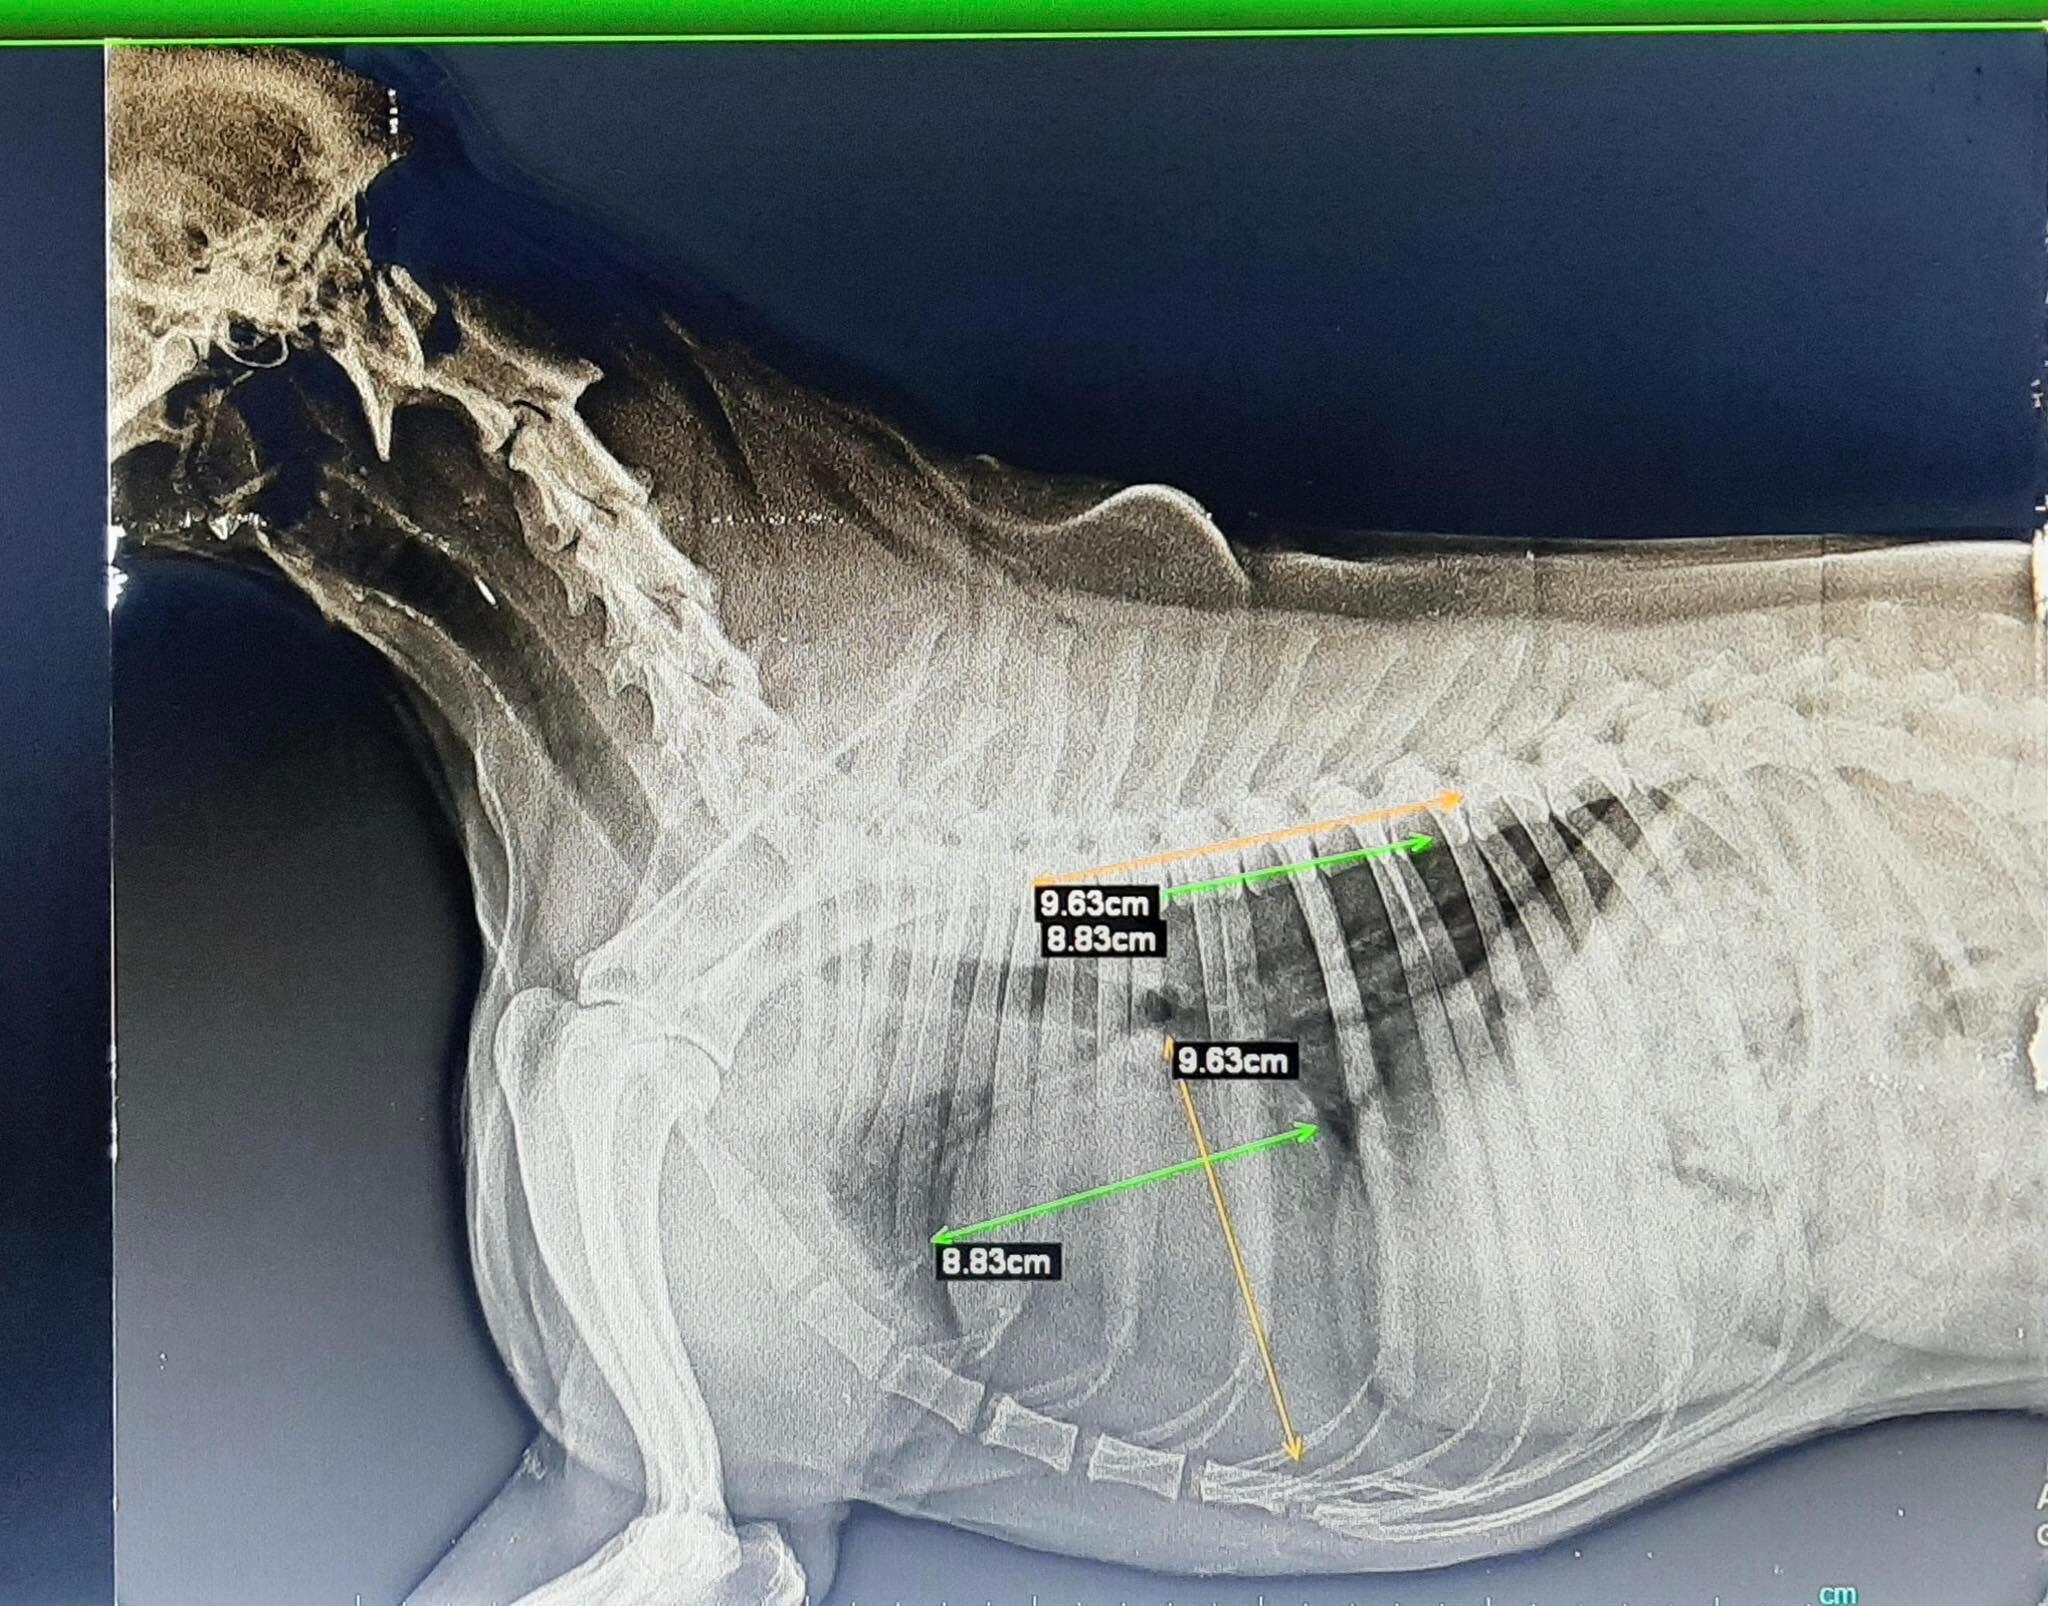

Hello. I have an issue with my 8-year-old English Cocker Spaniel. After some mild coughing, the vet found a throat irritation but also said that his heart had grown bigger (DCM). He said that the growth is not that big and put him on medication, but I wanted a second opinion. I attached a photo of the x-ray

Hello and thank you for using Pet Coach! Based on the radiograph you attached, the vertebral heart score (VHS) is on the larger measurement and overall the heart does have increased contact with the sternum. There does not appear to be evidence of heart failure, but I am limited with one x-ray view and no ability to adjust the contrast. I don't know what medication your veterinarian started Bono on but in this case, I would recommend starting omega 3 fish oil, Pimobendan (prescription medication that helps delay on the onset of heart failure and helps the heart pump more efficiently). I would also look into heart supplements such as Standard Process Whole Body Support and Cardiac support (if available in your country). Here is an article from my hospital on heart disease and what to look out for. Mitral valve disease is one of the most common heart conditions we see in dogs. I hope this helps and provides you with more information. If you have any concerns, I would reach out to the veterinarian who has been seeing Bono. https://www.neighborhoodvetclinic.com/degenerative-valve-disease-myxomatous-mitral-valve-disease/